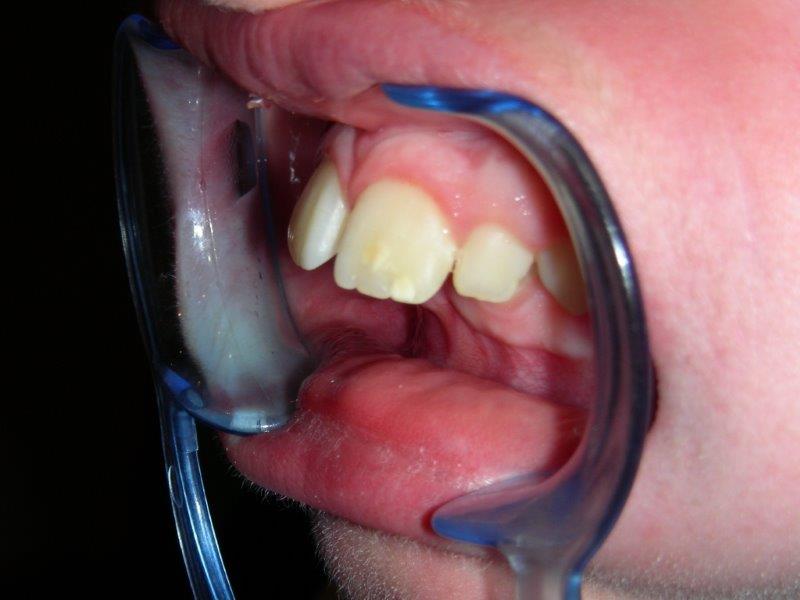

sobremordida1 SOBREMORDIDA, las paletas de arriba recubren completamente las de abajo. Las paletas inferiores pueden llegar a morder el paladar.

Es más difícil de ganar espacio en las arcadas y por ello, a veces es necesario extraer ciertas piezas.

El niño termina su crecimiento y la diferencia en las bases óseas es a menudo irreparable.